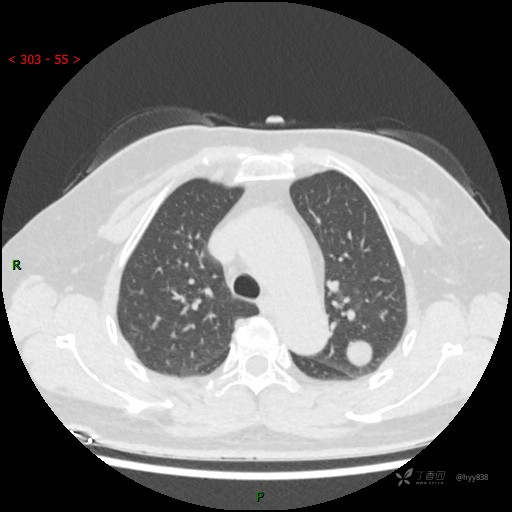

增强动脉期

各期CT值:28hu、58hu、69hu